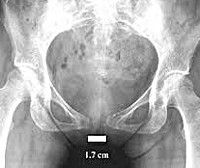

• Рентгенография тазовых костей. Проводится в послеродовом периоде. По рентгеновскому снимку легко уточняется расстояние между костями лобка, выявляются их возможные смещения в сторону и вверх/вниз по отношению друг к другу.